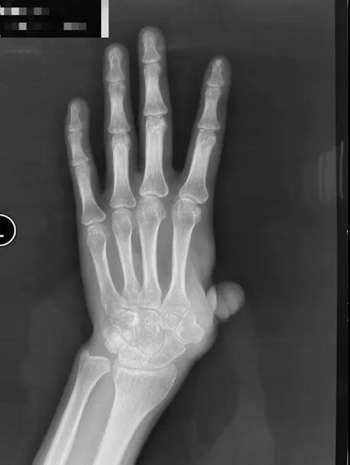

患者因机器伤导致左手拇指在掌骨水平近端离断,在外院进行了再植术,但术后手指存活情况欠佳,随后又做了游离踇甲瓣再造拇指,骨水泥置入等多次手术,但都没有成功保指。目前患者的左手拇指仅残留部分冗余皮肤,无掌骨,外观和功能都受到了极大的影响。

为了保住左手功能,患者慕名来到积水潭医院手外科就诊。陈山林主任检查后发现,他的左手第一系列缺失,若采用传统踇甲瓣结合髂骨移植等办法进行拇指再造,不仅重建的掌骨有被吸收掉的风险,而且患者无法获得有功能的腕掌关节,然而稳定且可活动的腕掌关节恰恰在发挥拇指功能中是最为重要的一环。考虑患者左手仍保留完整的大多角骨,陈山林团队决定为患者定制化制作金属3D打印的第一掌骨,满足患者第一腕掌关节的解剖学重建,为患者的拇指再造提供了一个良好的骨性基础。经文献检索,该技术属于世界首创!

对于外伤后拇指缺损的患者来说,重建拇指是非常有必要的,拇指功能对于手功能的完成非常重要。常规的拇指再造包括第二足趾游离移植,或是通过髂骨移植重建掌、指骨,再通过踇甲瓣重建拇指指甲和皮肤。也有改良的方式通过踇甲瓣嵌套第二足趾趾骨重建拇指。但不论哪种重建方式,都无法使患者获得具有活动的腕掌关节。而通过定制化的假体制作,即使形状不规则的腕掌关节,也可以达到完美的解剖学重建,使其获得活动。